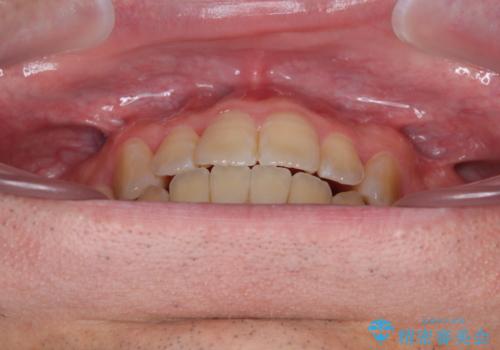

オープンバイトをインビザラインで矯正治療

- 前歯の開咬を気にして来院された患者様です。

開咬の治療は、前歯を閉じるように動かすとともに、上下臼歯を圧下(骨内にめり込ませる)させることで進めて行きます。

インビザラインは臼歯の圧下を効果的に行えるため、インビザラインを用いて矯正治療を行うこととしました。